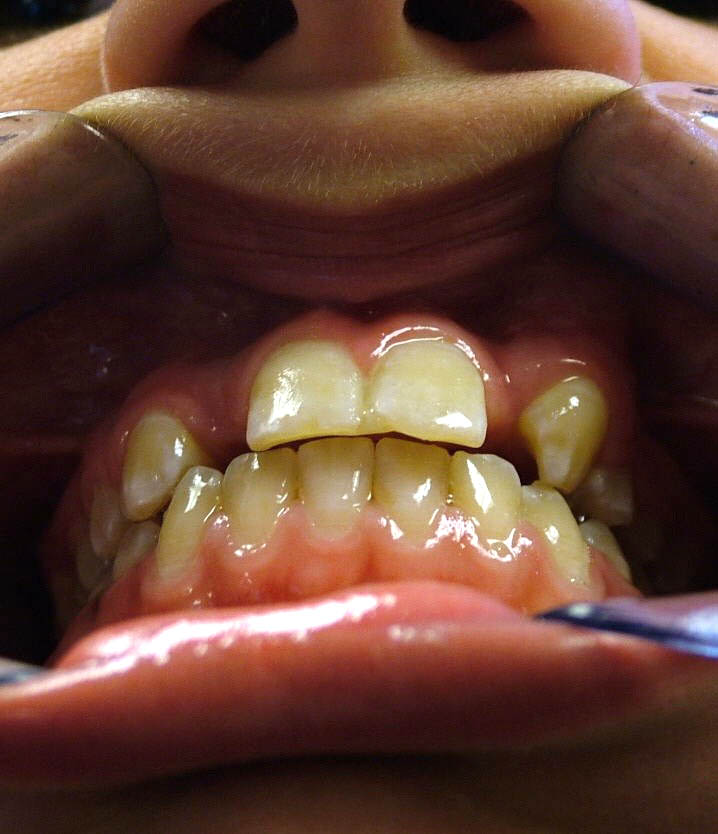

La momentul prezentării în clinică, în decembrie 2002, pacienta avea 8 ani şi o lună şi suferea de fibroză chistică şi de o deficienţă de dezvoltare a etajului mijlociu al feţei. Aceasta prezenta o anomalie de clasa I care mima o anomalie de clasa a III-a. Incisivii centrali, laterali şi caninii temporari maxilari, precum şi molarii prim şi secund de pe partea stângă erau în ocluzie inversă. În plus, pacienta prezenta coloraţii ale dinţilor de etiologie idiopatică (fig. 1). Autorii au considerat coloraţiile ca fiind de suprafaţă, extrinsece şi nu determinate de fibroza chistică, dovadă îndepărtarea acestora prin periaj profesional. Radiografia panoramică efectuată cu 6 luni înainte de prezentarea în clinica stomatologică relevă anodonţia incisivilor laterali superiori şi a premolarului secund drept inferior, ca şi posibila incluzie a caninilor maxilari, în special a celui stâng (fig. 2).

A doua etapă a tratamentului a fost amânată până în aprilie 2006, când pacienta a împlinit vârsta de 11 ani şi 5 luni. În acel moment, fetiţa prezenta erupţie şi dezvoltare radiculară adecvată, astfel că aparatele fixe aplicate acum n-ar fi purtate o perioadă îndelungată. Ocluzia inversă frontală şi angrenajul invers lateral fuseseră corectate; totuşi, exista o diastemă mare, în principal cauzată de lipsa incisivilor laterali superiori (fig.3). În acest moment, radiografia panoramică relevă anodonţia incisivilor laterali maxilari şi a premolarului secund drept mandibular, o anatomie redusă a rădăcinilor incisivilor centrali superiori, incluzia caninului superior stâng şi dezvoltarea întârziată a rădăcinii celui de-al doilea premolar inferior (fig. 4).